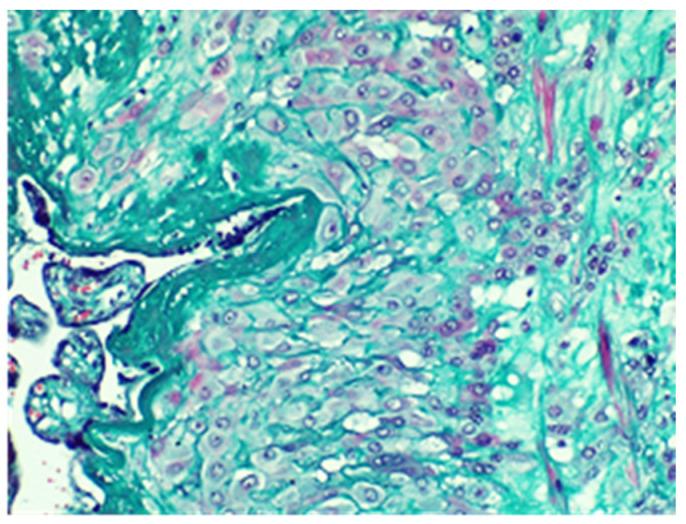

Placental morbid adherence is a known risk factor for postpartum hemorrhage. The incidence of abnormal placental attachment has been increasing over the past few decades, mainly due to rising rates of cesarean deliveries, advanced maternal age, and the use of assisted reproductive technologies. Cesarean section is a significant risk factor for placenta increta, as it disrupts the normal architecture of the uterine wall, making it more difficult for the placenta to detach after delivery. We present the case of a woman who underwent a cesarean section at 28 weeks due to anterior placenta previa, accompanied by hemorrhage and rupture of membranes. Following the delivery, she experienced normal postoperative bleeding and was discharged home after five days. However, six weeks later, she presented with heavy bleeding, leading to the decision to perform a total hysterectomy. The levels of HCG were found to be low. The pathological examination of the specimens confirmed a diagnosis of placenta increta, as it revealed notable placental proliferation, necrotic villi, and placental invasion near the uterine serosa. Notably, we did not find any similar cases documented in the literature. Patients experiencing prolonged vaginal bleeding after childbirth and diagnosed with placenta accreta should be closely monitored through ultrasound examinations; abnormal proliferation of the placenta can occur, and prompt detection is crucial for appropriate management.

胎盘植入是产后出血的已知危险因素。在过去几十年中,异常胎盘附着的发生率一直在上升,主要是由于剖宫产率上升、产妇年龄增大以及辅助生殖技术的使用。剖宫产是胎盘植入的一个重要危险因素,因为它破坏了子宫壁的正常结构,使得胎盘在分娩后更难剥离。我们报告一例因前置胎盘于孕28周行剖宫产的妇女病例,术中伴有出血和胎膜破裂。分娩后,她术后出血正常,五天后出院。然而,六周后,她出现大量出血,遂决定行全子宫切除术。发现血HCG水平较低。标本的病理检查证实为胎盘植入,因为它显示出明显的胎盘增生、坏死绒毛以及子宫浆膜附近的胎盘侵入。值得注意的是,我们在文献中未发现任何类似病例的记载。产后出现长时间阴道出血且诊断为胎盘植入的患者应通过超声检查密切监测;胎盘可能会出现异常增生,及时发现对于恰当的处理至关重要。